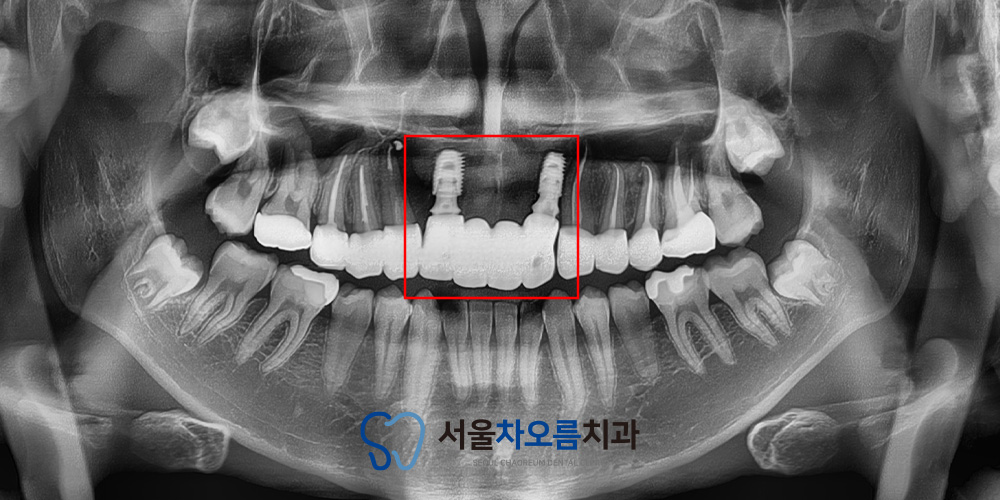

25.02.06

앞니 부분이라 심미적인 부분을

빠르게 개선하기 위해

발치를 하며 즉시 식립을 진행하였습니다.

또한 발치 후 식립하면

잇몸뼈가 꺼질 수 있기 때문에

뼈이식을 진행하여 임플란트가

안정적으로 고정될 수 있도록

지원했습니다.

뼈이식을 통해

잇몸뼈의 양과 질을 확보하고,

장기적으로 안정적인 임플란트

식립이 가능하도록

만들어주었습니다.

총 2개를 식립하여

추후 보철이 4개로

연결될 수 있도록 하였습니다.